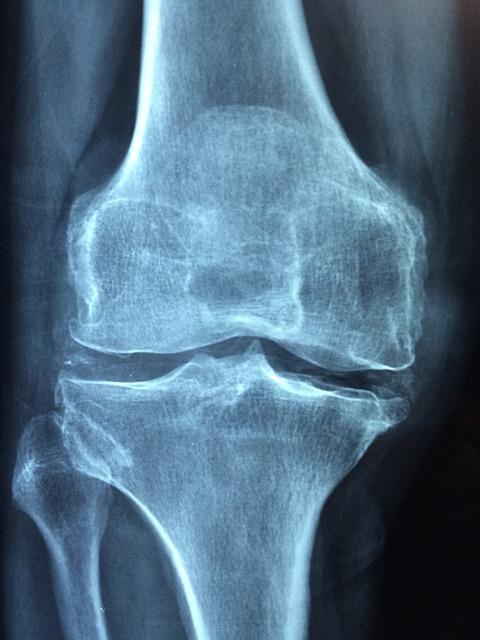

- Rentgenové snímky: Pomocí rentgenů lze odhalit možné degenerativní změny, zlomeniny nebo artritidu.